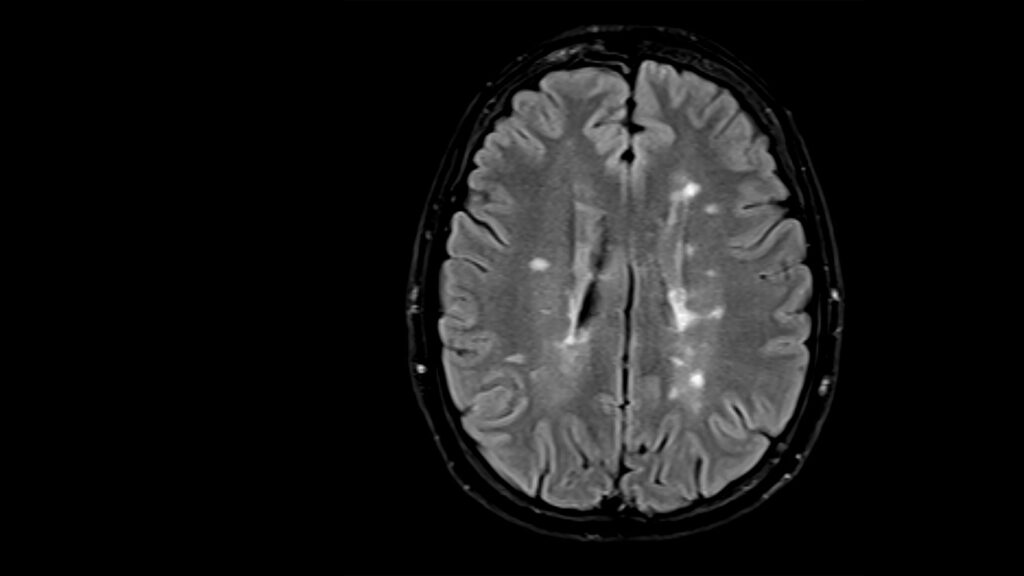

Microsoft is developing machine learning based techniques that can reconstruct medical images from raw datasets that are incomplete (undersampled) or corrupted by artifacts. We believe that machine learning will play a critical role in accelerating medical image acquisitions and improving the patient experience, and are particularly interested in how well machine learning based image reconstruction does in reconstruction of clinically relevant details and lesions. We have curated annotations for clinically relevant lesions (opens in new tab) and are using such annotations to optimize reconstructions and workflow.